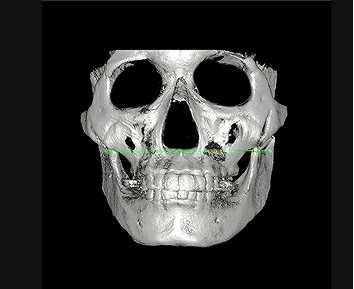

Targeting the areas with the greatest protrusion

ID Hospital’s contouring revision surgery reduces the most protruding areas

of the cheekbone using the High-L osteotomy/reduction method,

minimizing excessive bone removal while effectively reducing volume.

Jaw angle revision surgery addresses the maximal volume point (MVP) that defines the jawline, reducing it to create a slimmer and more refined

facial contour visible from every angle.